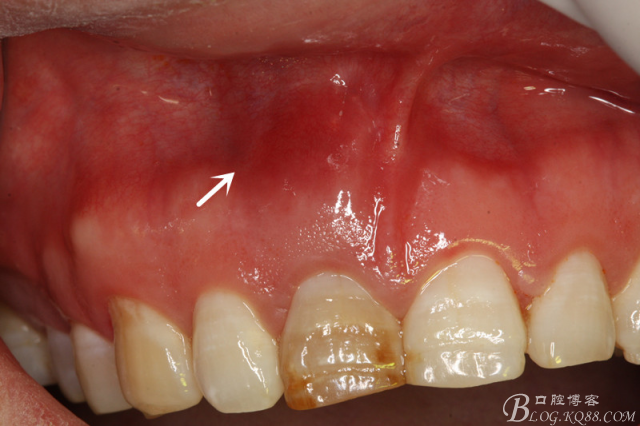

圖15. 11MTA完成倒充填后的影像